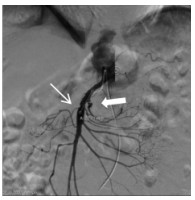

消毒右侧腹股沟区,经右侧股动脉入路。经穿刺点置入5F血管鞘,0.035 -in导丝引导5F Cobra导管进入SMA近端,造影(造影剂速度4~6 mL/s,时间3~4 s),明确病变位置及肠系膜远端血供情况。造影可见SMA近端呈夹层样改变(图 2细箭头示),空肠动脉分支近端呈假性动脉瘤样改变(图 2粗箭头示),虽然有夹层出现,但SMA主干全程尚通畅。更换8F血管鞘,应用导管导丝技术送入肝素涂层血管内覆膜支架(7 mm×25 mm)覆盖于夹层段并造影,发现病变段未完全封闭(图 3细箭头示)。主要由于为尽量减少支架对远端正常分支血管的影响,第一枚支架长度略短,因此再植入一枚支架(8 mm×25 mm)与第一枚叠加。再次经SMA造影,发现SMA主干内对比剂滞留(图 4),SMA中主干远端及其分支血管未显影。同时患者出现腹痛加重、气促、心率减慢至约40~50次/min,血压高压达到180/100 mmHg,考虑患者发生急性动脉血栓形成。紧急予面罩吸氧,静脉注射阿托品肌0.5 mg。经导管于SMA应用尿激酶25万U、肝素3 000 U进行持续灌注,灌注时间约5~8 min。应用球囊(8 mm×50 mm)扩张支架。最后再次经SMA造影,可见SMA主干近端再通,夹层瓣膜及其附近病变空回肠血管未再显影。病变远端空回肠动脉分支大部分恢复通畅(图 5粗箭头示),但SMA主干远端部分血管仍有部分未溶解血栓(图 5细箭头示),术后回病房每天皮下注射低分子肝素钙2 500单位,2次/d;患者腹痛症状当即减轻,生命体征恢复正常。

| 图 2 造影可见SMA主干内夹层(细箭头示),夹层附近空回肠动脉近端瘤样扩张(粗箭头示) |